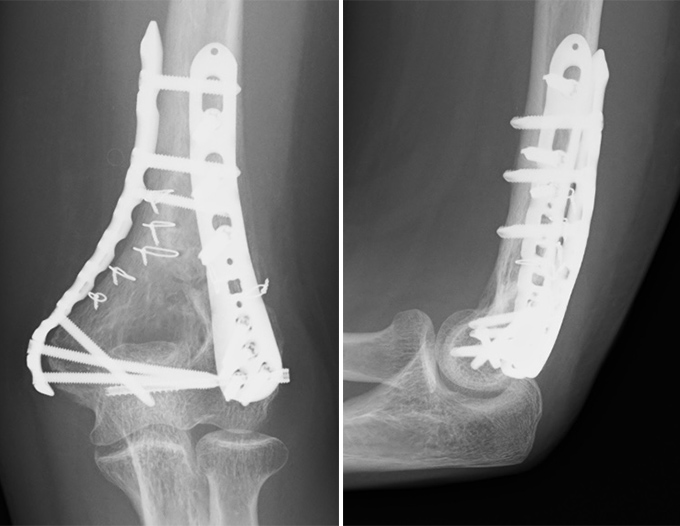

肘頭骨折

肘の尖った部分(肘頭)が折れる外傷で、転倒して肘を強くついた際などに起こります。肘頭には上腕三頭筋が付着しており、牽引によって骨片が離開するため、痛みや腫れが強く、肘を伸ばすことが困難になります。ずれが少ない骨折ではギプス固定で自然治癒を目指しますが、多くの場合は筋力により骨折部が引き離される力が加わるため手術を要します。ワイヤーやプレートで固定する従来の方法に加え、当科では骨折型によって金属を用いずに強力な縫合糸で固定する方法も行っております。強固に固定することで術後早期からリハビリを行い肘の可動域の再獲得を目指します。

症例① 70代 女性 プレート固定

症例② 70代 女性 dual suture fixation